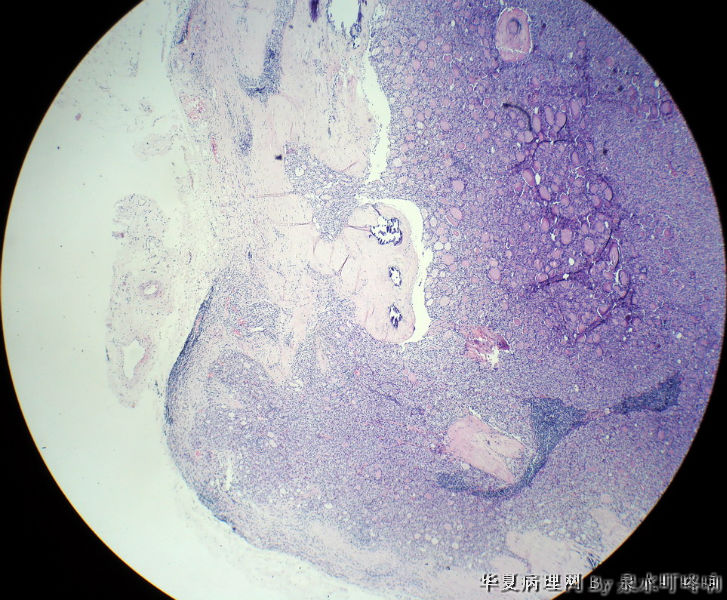

120212,女,55岁,左颈部肿物七年余。

大体:灰白肿物一个,大小约2.1×1.5×1.3厘米。表面光滑,包膜完整,切面灰白,部分包膜有钙化。

与手术医生沟通,肿物位于左颈部靠近甲状腺部位,比较浅(门诊手术),手术医生认为是淋巴结部位。

厚包膜、蕈状浸润----滤泡癌。